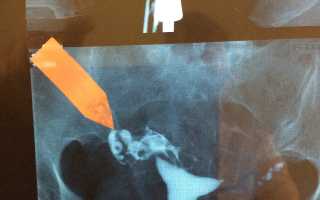

Левая маточная труба в ампуле непроходима.

Правая маточная труба проходит с трудом из-за наличия справа сактосальпинксного клапана.

Стрелкой справа показан клапан сактосальпинкса.

Буква «R» на изображении указывает на правую сторону пациента.